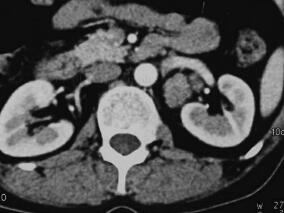

继发于甲状旁腺腺瘤的肾结石1例

1小时条评论【病例资料】 患者男性,50岁。 主诉:体检发现右肾结石1个月。 现病史:患者1个月前于当地医院体检时发现右肾结石,具体情况不详。患者无发热,无腰痛、腹痛,无肉眼血尿,无尿频、尿急、尿痛症状。当地医院诊断:右肾结石。患者接受体外冲击波碎石治疗两次,自...